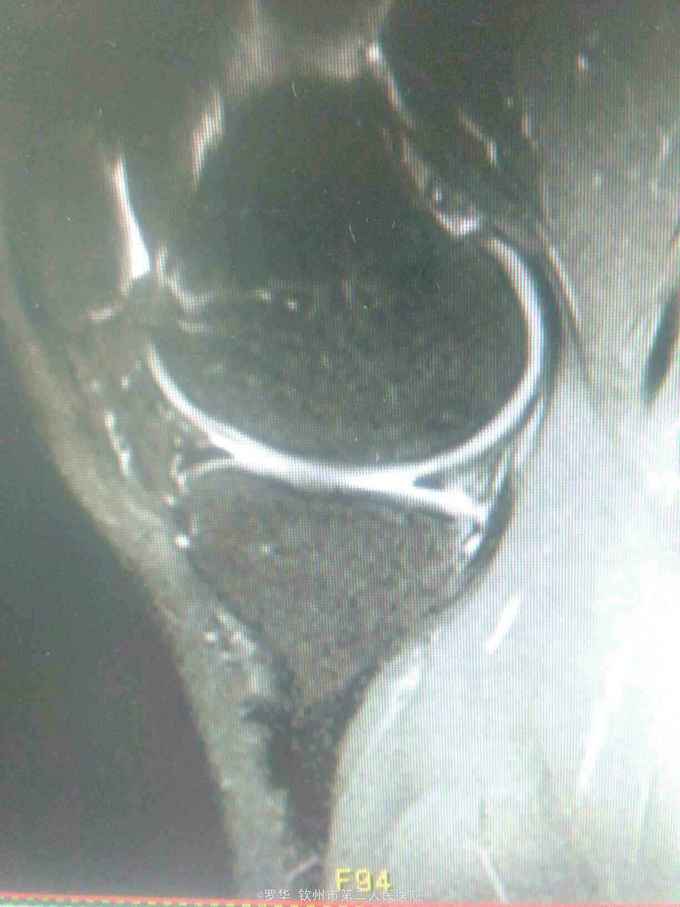

主诉:扭伤致左膝关节活动受限3月余。病史:患者男性,31岁,于入院3月余前扭伤左膝关节,致左膝关节肿痛、活动受限,尚可站立行走,但不能剧烈运动及重体力劳动,曾行磁共振检查提示左膝前交叉韧带损伤,半月板损伤,现为进上一步治疗入院。

查体:左膝关节无明显压痛,前抽屉试验阳性,侧方应力试验、麦氏征、研磨试验均阴性,膝关节屈伸活动可,余查体未见特殊。 辅查:膝关节磁共振提示左前交叉韧带损伤,左膝关节半月板损伤。

诊断:左膝关节前交叉韧带断裂,左膝关节半月板损伤。 治疗:予硬外麻下行左膝关节前交叉韧带重建术。